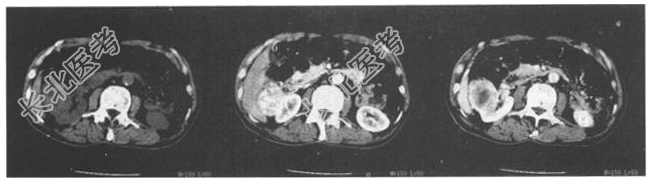

- [材料题] 患者,男,65岁。全程无痛性血尿半年,不伴尿急、尿痛;半年反复肉眼血尿,尿常规示:红细胞4~5/HP,白细胞0~2/HP,蛋白(+),查体:双肾区叩击痛阴性,尿道未见异常。

- 简答题2、CT检查所示如下图,诊断为?